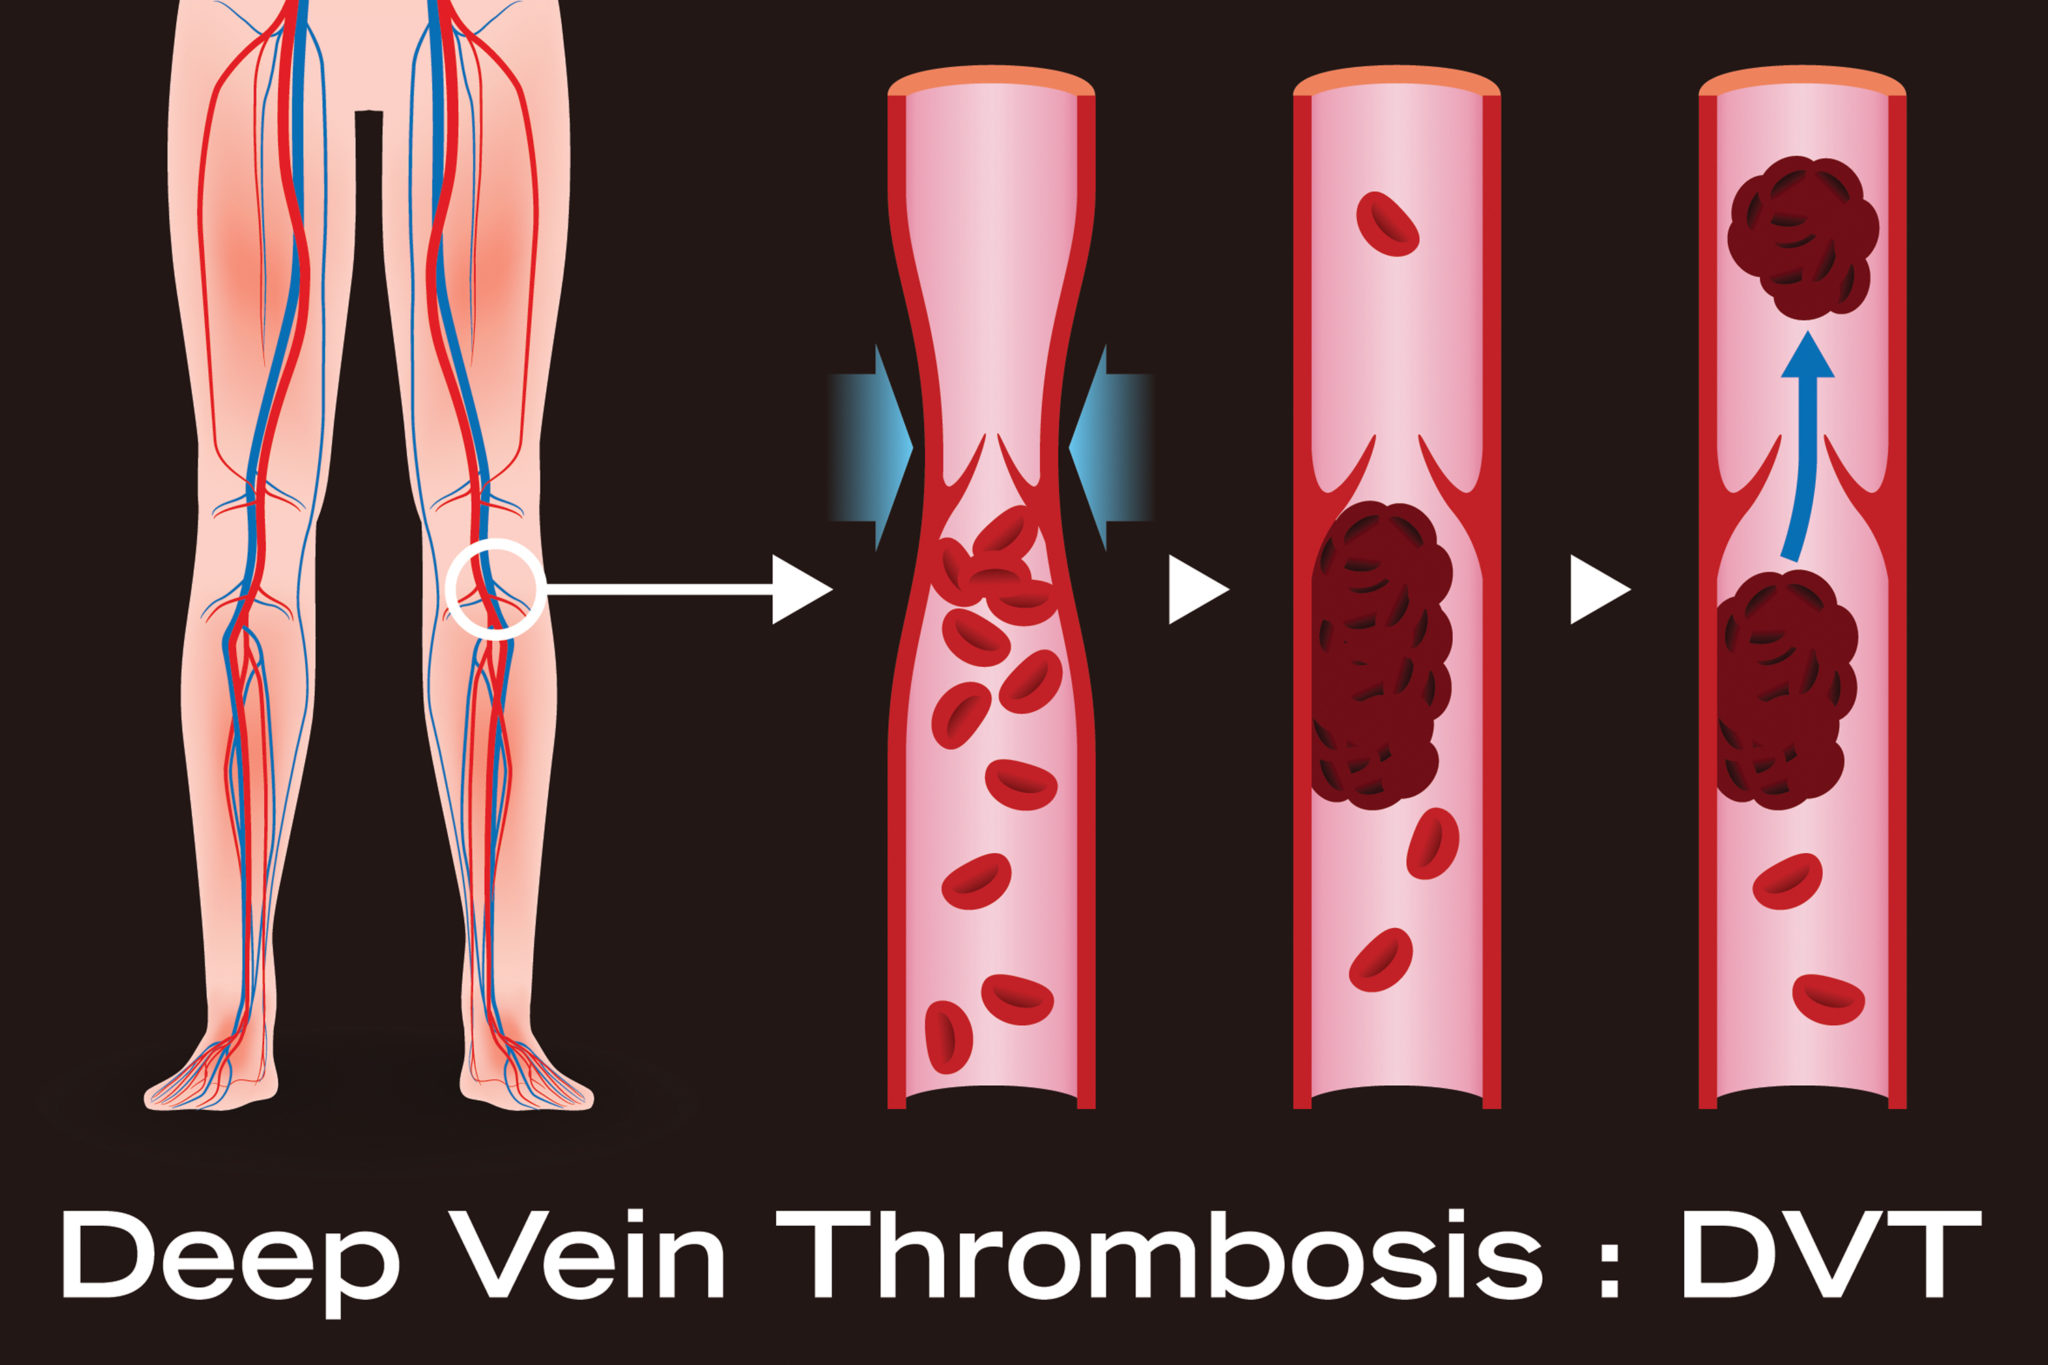

dvt thrombosis vein

thrombosis vein dvt veins embolism pulmonary drugwatch lungs vessel

vein thrombosis dvt venous vte hmp thromboembolism

vein thrombosis deep venous thromboembolism treatment prevention femoral common thrombus distal proximal knee ppt secondary powerpoint presentation